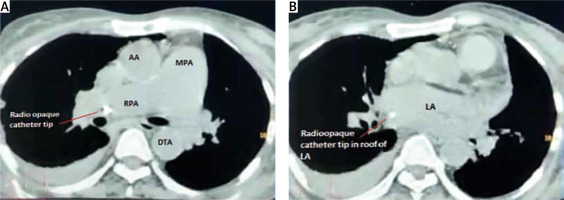

A 51-year-old chronic kidney disease patient with chronic obstructive pulmonary disease underwent catheter insertion with a Hemosplit 14.5 Fr haemodialysis catheter (Bard Access Systems, Utah, USA) through the right subclavian vein in the nephrology unit of our institute. The procedure was conducted with good flow through one port and poor flow through the other port. The catheter guidewire was removed completely but was seen to be coiled on extraction. Some amount of force was also required during the insertion of the catheter as reported by the operator. A post-procedural chest X-ray showed normal position of the catheter. Anticipating that the poor flow through one port could be due to abutment of the catheter against the vessel wall or due to a clot and because of the normal X-ray (Figure 1), the patient was taken for haemodialysis. Two hours into dialysis, the patient became hypotensive with a systolic blood pressure of 70 mm Hg. Dialysis was immediately terminated and imaging in the form of non-contrast neck and chest computed tomography (CT) in view of the patient’s renal status was done. It showed the catheter entering through the right supraclavicular region traversing posterior to the medial end of the clavicle, right subclavian vein, superior vena cava and traversing in the right part of the middle mediastinum. The catheter was seen in close contact with the right pulmonary artery and left atrium with air foci adjacent to the catheter in the left atrium (Figures 2 A, B). As attempts at haemodynamic stabilisation did not succeed, the patient was taken immediately into the operation theatre for exploration by the cardiovascular and thoracic surgery department.

Figure 2

A – Catheter seen in the right pulmonary artery on non-contrast CT chest. B – Catheter seen in the left atrium on non-contrast CT chest

LA – left atrium, MPA – main pulmonary artery, RPA – right pulmonary artery, AA – ascending aorta, DTA – descending thoracic aorta.